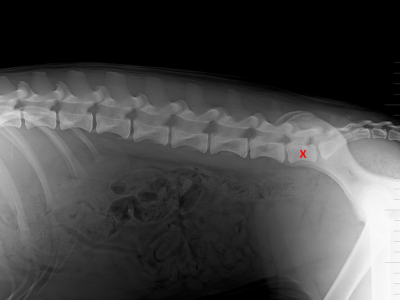

Lumbosakrální přechodový obratel

článek ze Zpravodaje 1/23